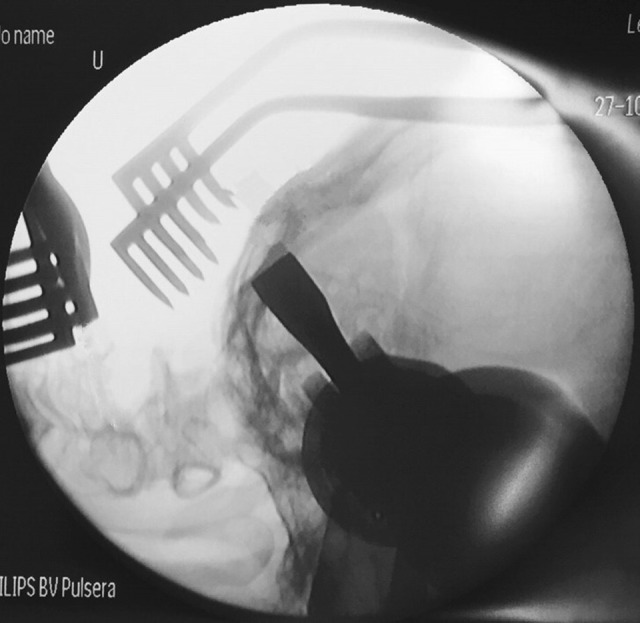

Fig. 5.

Intraoperative imaging showed realignment of atlantoaxial position after reduction